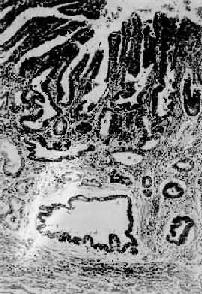

图10-10 早期胃癌

癌变局限于胃粘膜内,未超出粘膜肌层